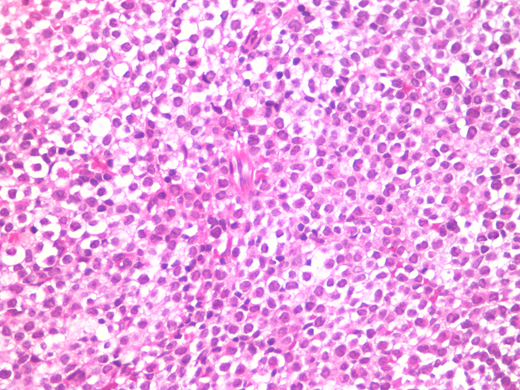

A 25-year-old woman with ongoing treatment for chronic myeloid leukaemia (CML) in use of Imatinib. Presented to the ER with fever, metrorrhagia, splenomegaly, cutaneous mycosis by Fusarium sp. Investigation upon admission showed pancytopenia, complete blood count showed white blood cells 1.290/mm3, hemoglobin 7,5 g/dL and platelets 13.000/mm3. Bone marrow trephine biopsy showed diffuse infiltration by blasts with large nuclei - round to oval, some irregular, some invaginated- and with hypergranulated cytoplasm(Fig. 01). The bone marrow aspiration showed hypocelular marrow with 67,9% pathological blasts (MPO++, CD13+, CD33++, CD117+, , CD34 -/+, CD15-, CD11b-). Chromosome analysis displayed 46, XX, t(9;22) (q34;q11) and t(15;17)(q22;q11-12). PCR showed amplification for both PML/RARα and BCR/ABL.